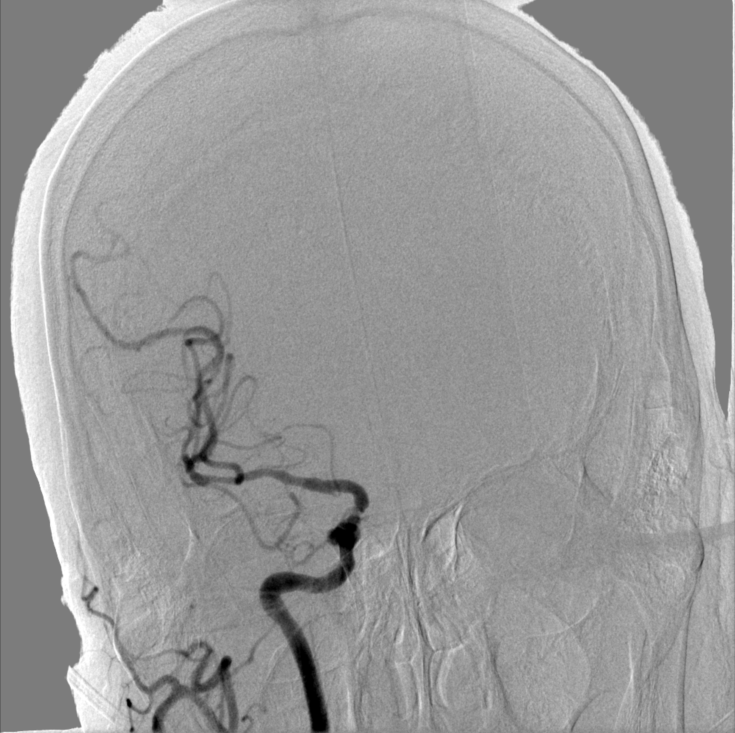

术后造影:

左侧颈内动脉C1段残余狭窄约10%,远端血管显影良好,前向血流mTICI 3级,未见远端血管栓塞及造影剂外渗。